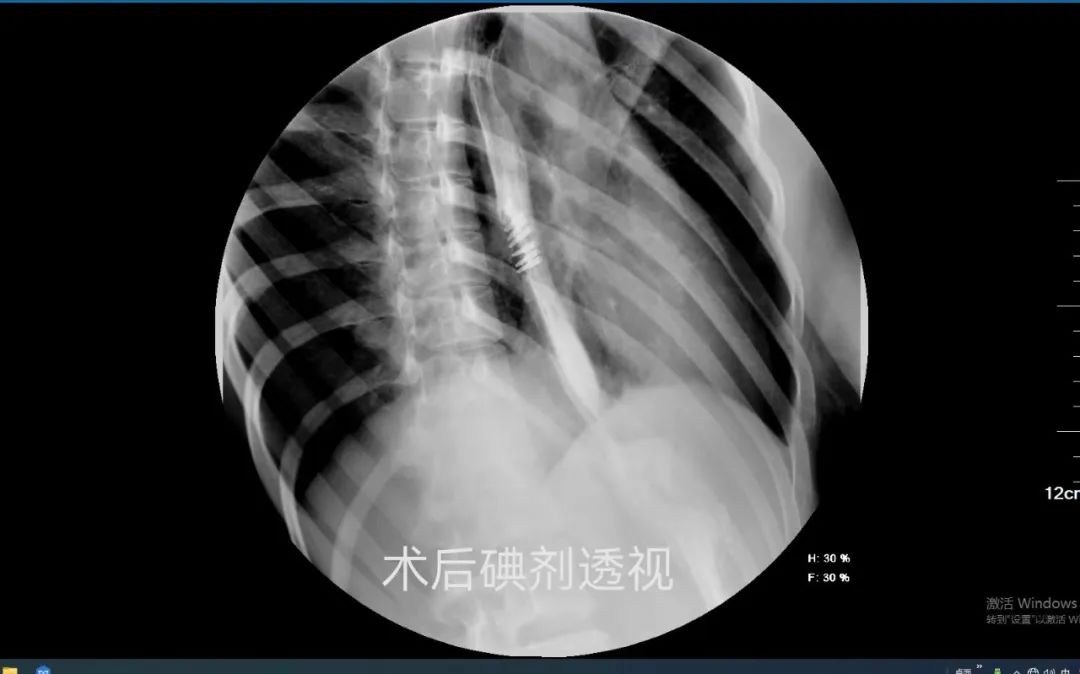

张先生,20岁,4年前开始出现进食梗阻感。为解决进食困难,他曾多次在多家医院就诊。最后,他慕名来到我院普外临床医学中心。经过详细的术前检查评估,患者顺利接受了经口内镜下食管括约肌切开术(POEM 术)。术后第三天,患者在喝水时就感觉胸口一下子“松快”了。之后经评估可进食,吞咽困难的症状完全改善。